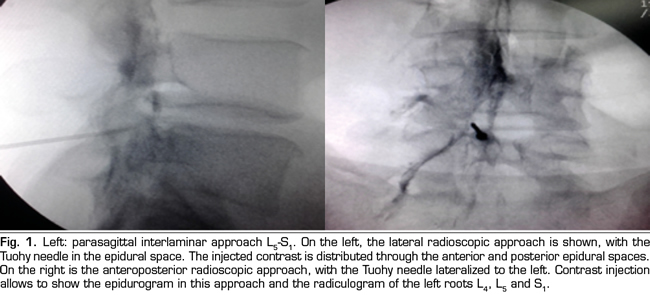

The final position of the needle in the oblique view was the subpedicular zone, while in the lateral view was the anterior superior angle or the roof of the neuroforamen, in the so-called safety triangle (Figure 2). The contrast volume injected was equivalent to the performed in the interlaminar group, obtaining a radiculogram and epidurogram after the injection (Figure 2). The solution of betamethasone was the same used in the interlaminar group, injecting the total volume of the solution in one or two levels, depending on clinical criteria.